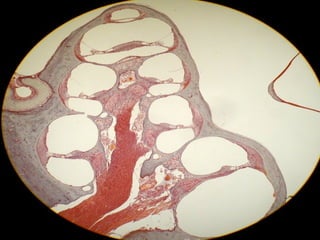

Laberinto

Membranoso

Cúpula

Crestas

Ampollares

Canales

Semicirculares

Conductos Semicirculares

Espacio con

Perilinfa

Endolinfa